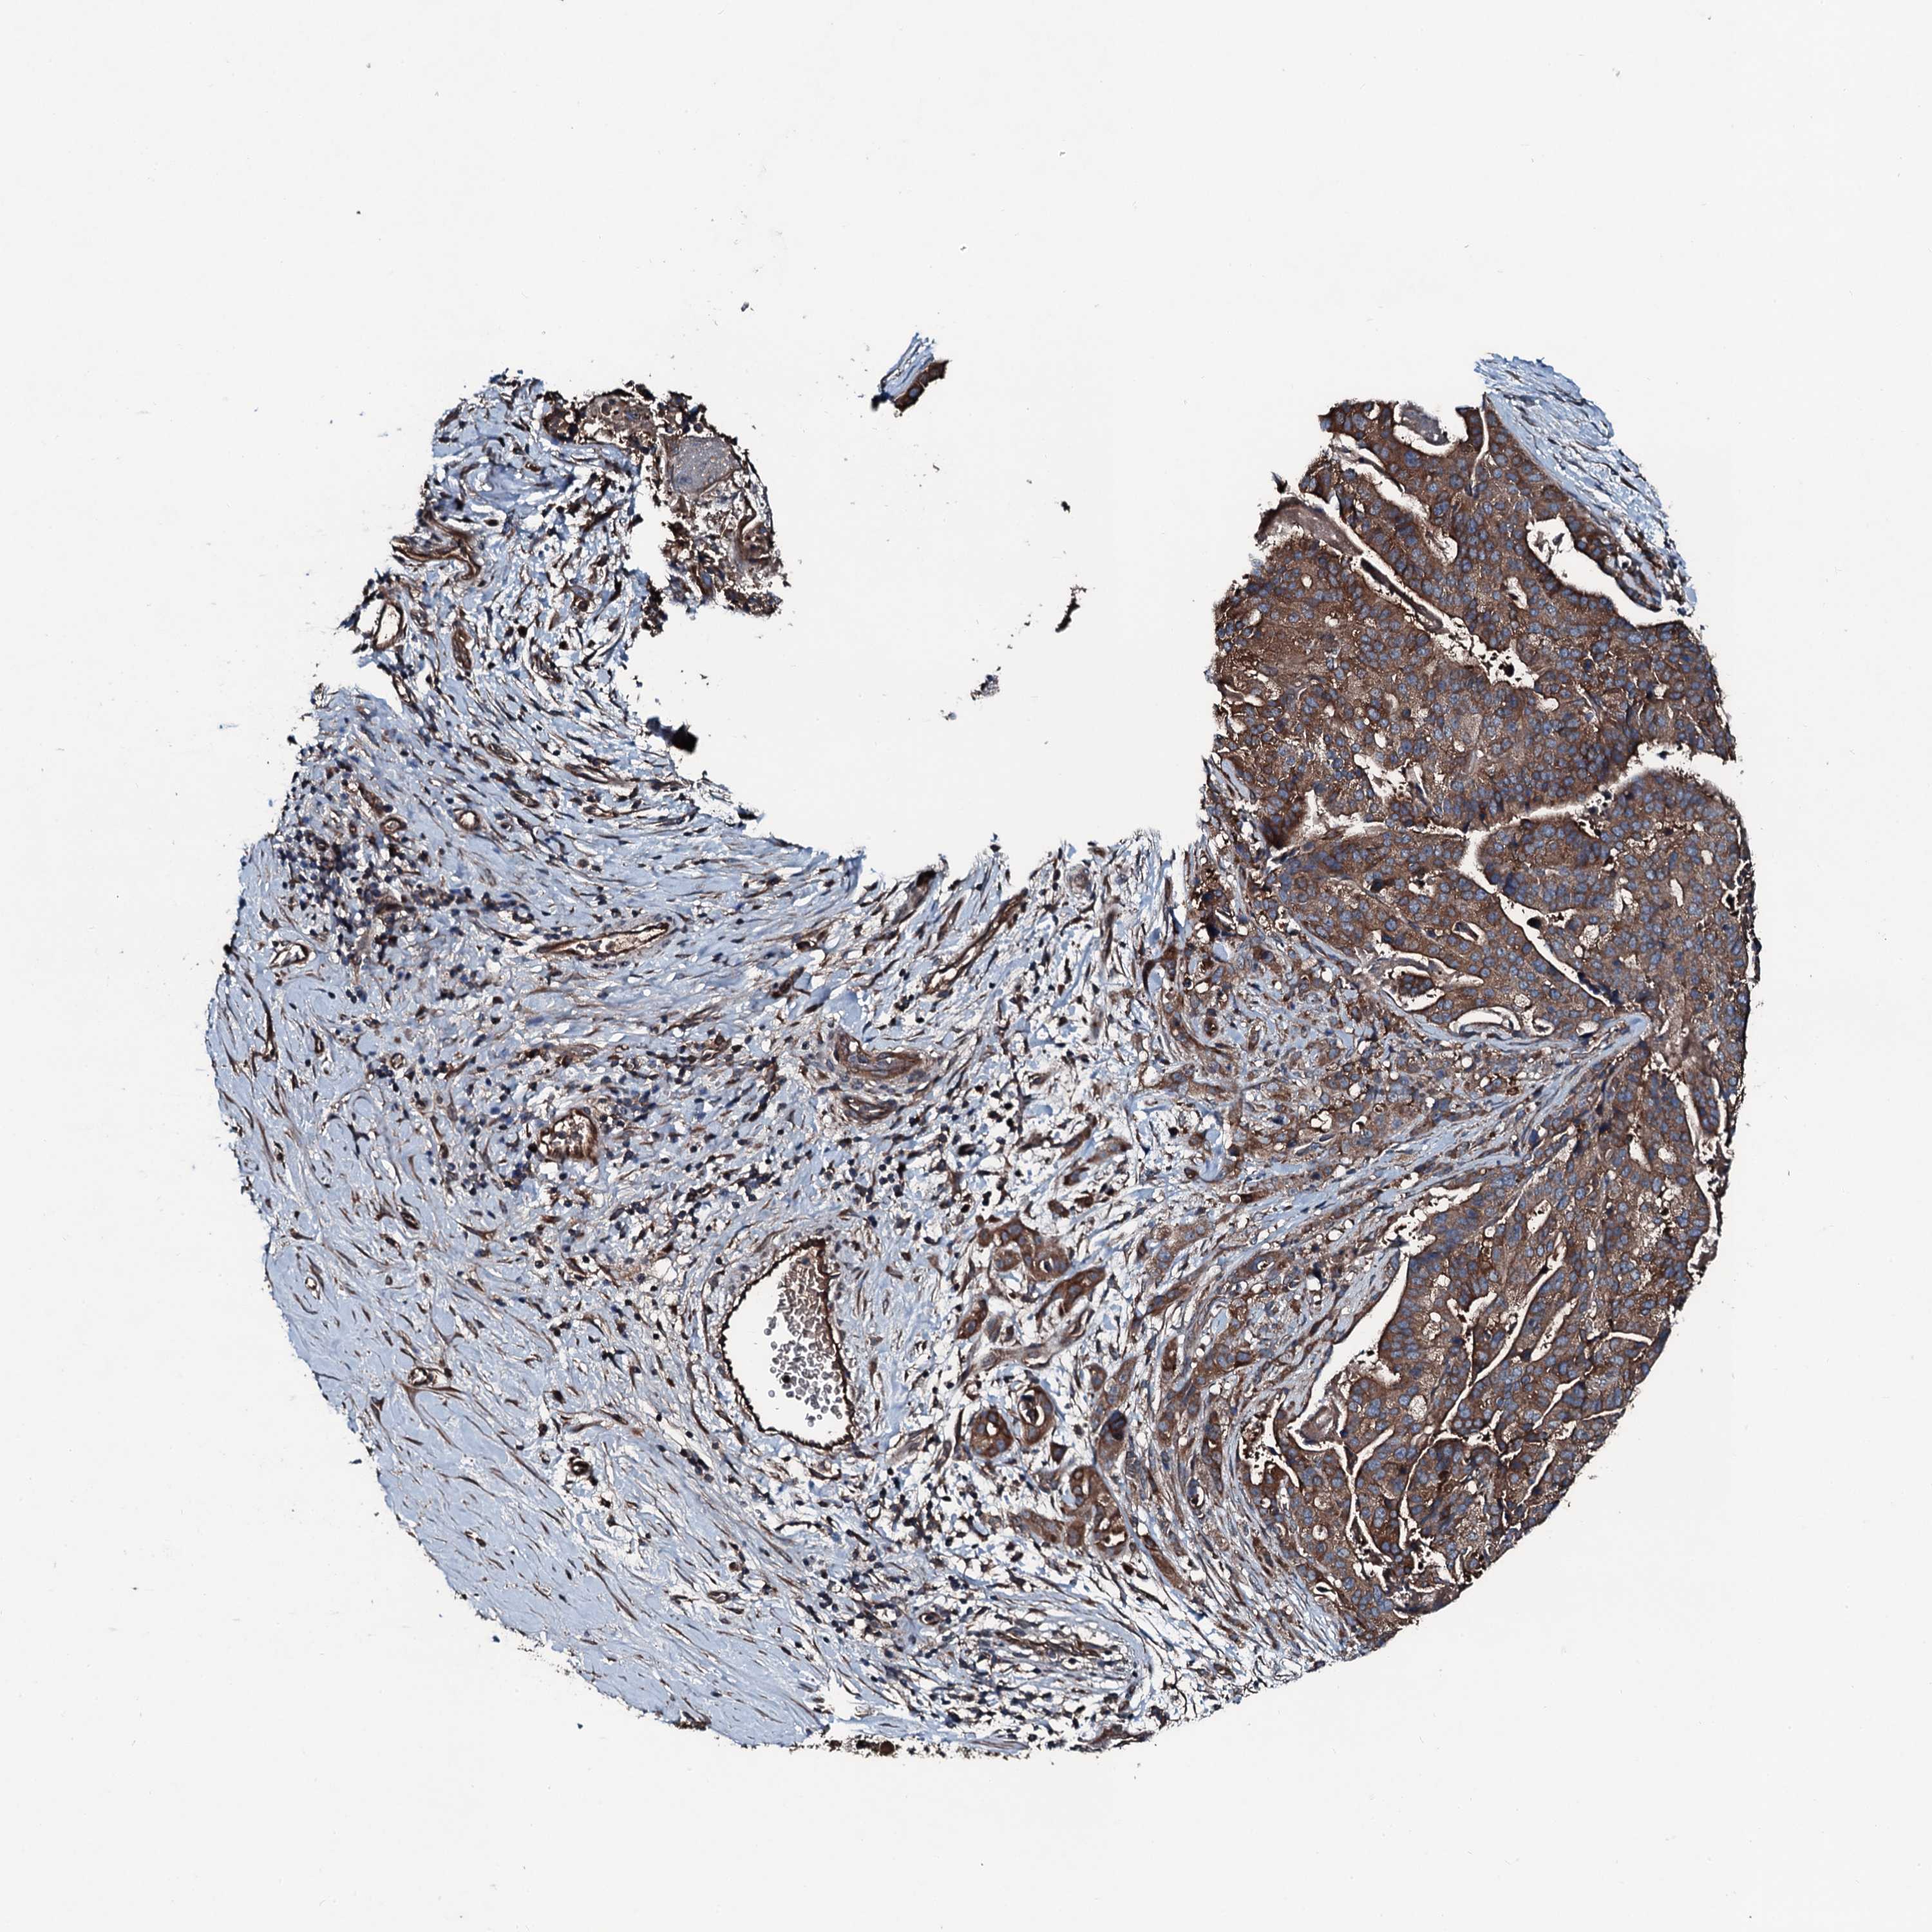

STOMACH CANCER - Protein expressioni

A mouse-over function shows sample information and annotation data. Click on an image to view it in a full screen mode. Samples can be filtered based on level of antibody staining by selecting one or several of the following categories: high, medium, low and not detected. The assay and annotation is described here.

Note that samples used for immunohistochemistry by the Human Protein Atlas do not correspond to samples in the TCGA dataset.

Antibody stainingi

Antibody staining in the annotated cell types in the current human tissue is reported as not detected, low, medium, or high, based on conventional immunohistochemistry profiling in selected tissues. This score is based on the combination of the staining intensity and fraction of stained cells.

Each image is clickable and will lead to virtual microscopy that enables deeper exploration of all samples and also displays staining intensity scores, fraction scores and subcellular localization as well as patient and tissue information for each sample.

Antibody CAB034261

Staining

High

Medium

Low

Not detected

Intensity

Strong

Moderate

Weak

Negative

Quantity

>75%

75%-25%

<25%

None

Location

Nuclear

Cytoplasmic/membranous

Cytoplasmic/membranous,nuclear

Adenocarcinoma, NOS

Adenocarcinoma, High grade